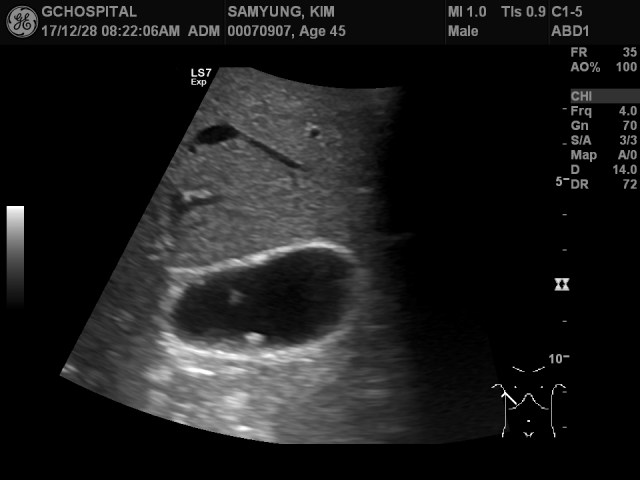

그리고, 이 영상이 환자를 엎드리게 해서 우측 posterior axillar portion에다 탐촉자를 대고 쓸개쪽으로 intercostal approach로 스캔한 영상입니다. 이 영상을 얻기 전까지 앞서의 고에코 병변을 네 개 정도 발견한 상태였는데, 이 영상 하나에서만 예닐곱개 이상의 많은 고에코음영의 폴립들을 확인할 수 있습니다. 물론, 탐촉자와 쓸개까지의 거리가 멀어서 해상도는 떨어지지만, 앞서의 자세에서는 보이지 않던 병변들이 추가로 여러개 발견되었다는 건 시사하는 바가 큽니다.